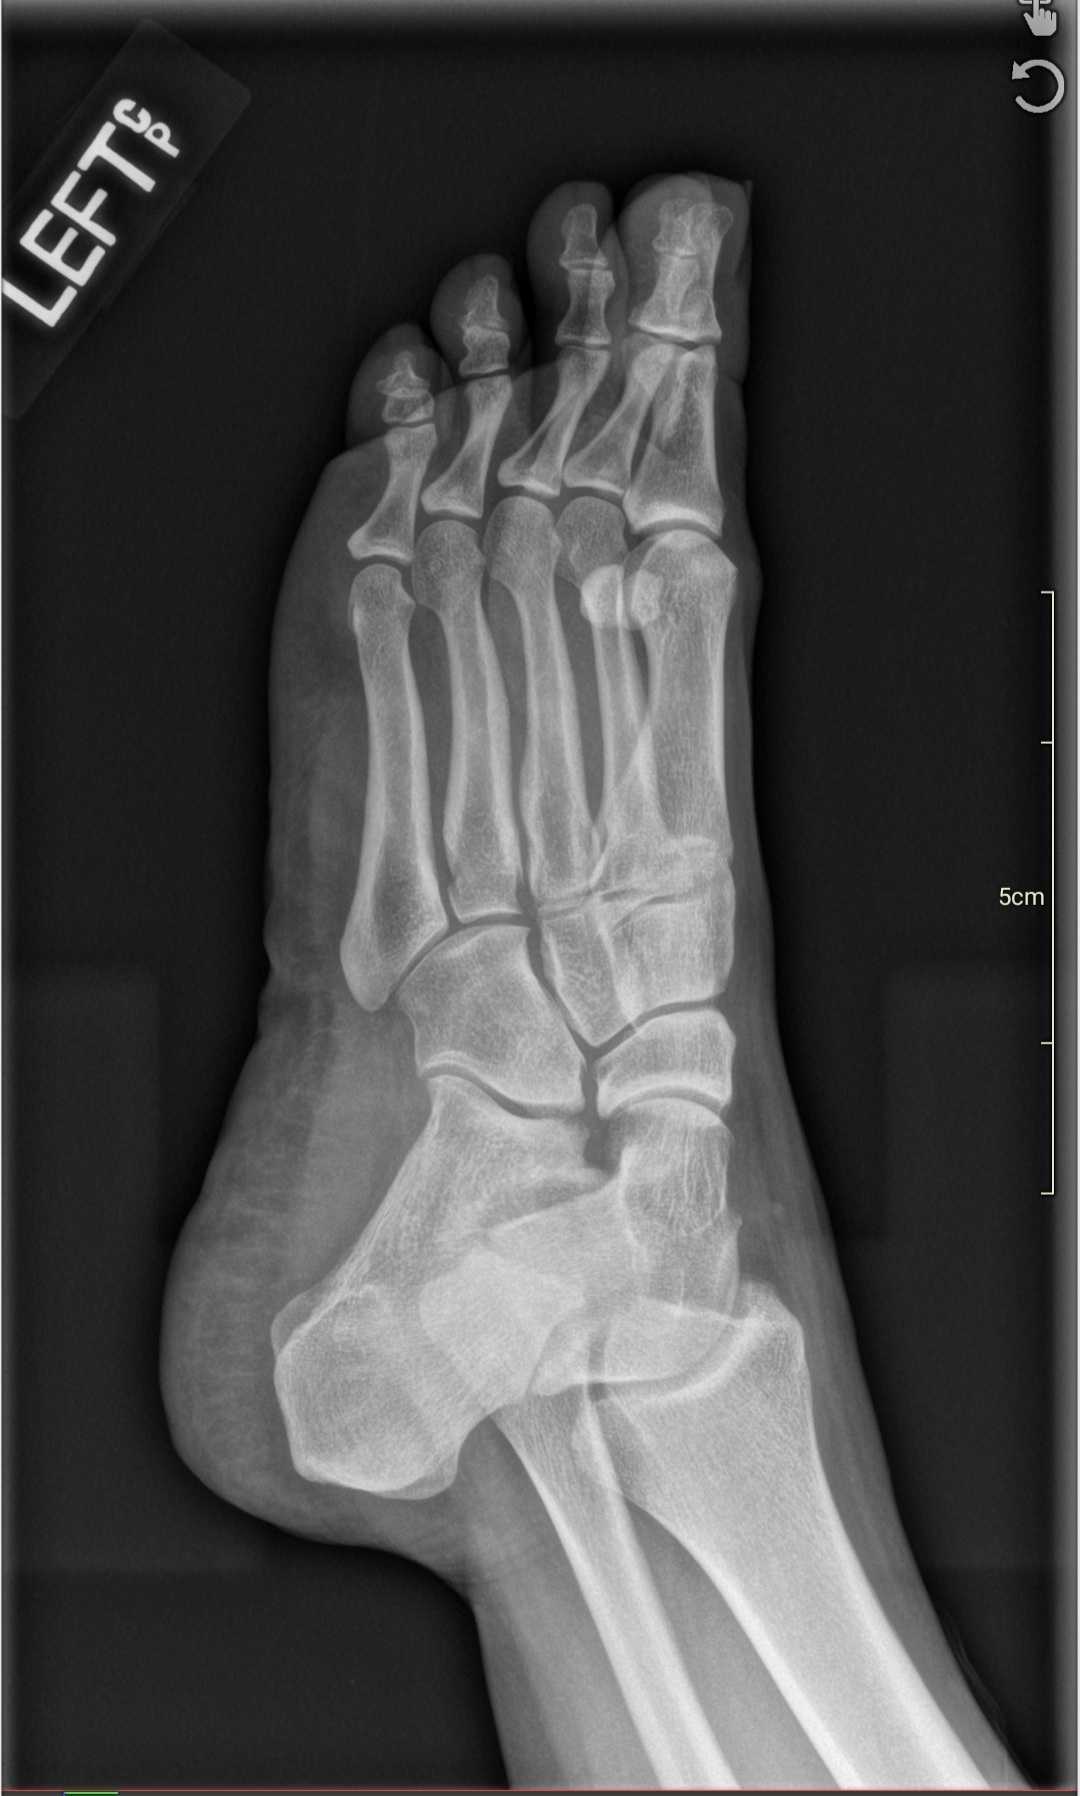

In my follow-up visit a week later with my care team after my neck x-rays, I also mentioned my on-and-off left foot pain.

I get pain in my left heel and in between my third and fourth toe. Sometimes it hurts for days, especially when I’m doing too much on my feet, like dancing.

I’ve had it for years and I have mentioned it to Primary Care once before. I usually forget to bring it up, though, because it usually goes away in a few days and I figured it was normal everyday wear. My doctored ordered x-rays of my left foot and insoles for my shoes.

In those X-rays, we can see a bone spur on my left foot heel – a calcaneal heel spur – that has been causing me pain when I put pressure on my heel. This can stem from Plantar Fasciitis – degeneration of the band of tissue (fascia) at the bottom of your feet that runs from your heel to your toes.

I’ve been given insoles for my shoes and told to only wear sneakers for a few weeks to see if it helps.